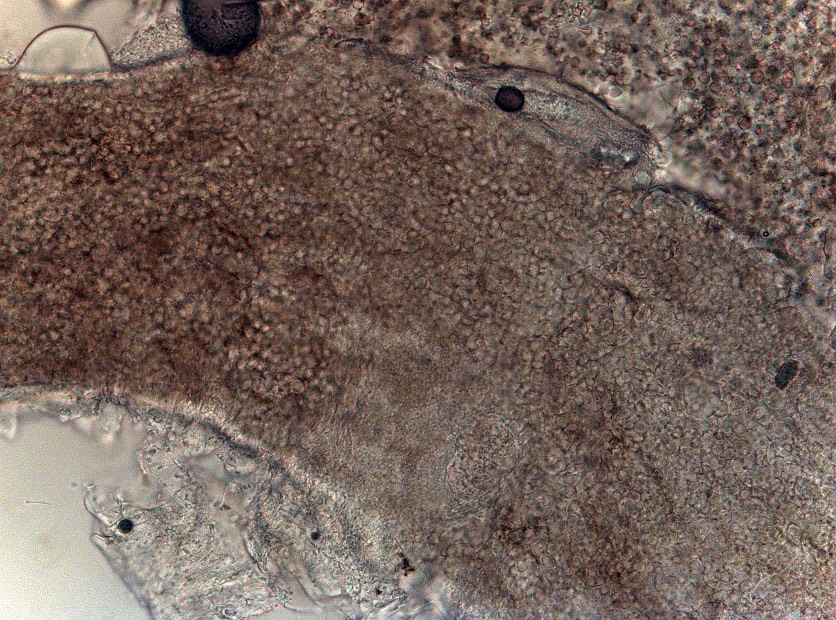

2059. При микроскопии пораженных волос при увеличении x400 виден тип роста дерматомицета